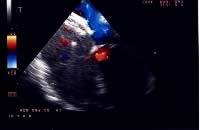

La procedura di impianto viene eseguita in anestesia generale con intubazione del paziente. Un ruolo essenziale, in tutte le fasi della procedura, è svolto dall’ecocardiografia transesofagea. Essa detta le indicazioni alla “fattibilità” (diametro del difetto, misura dei rims settali, ritorni venosi, anatomia atriale), guida l’operatore nel posizionamento della protesi a cavallo del difetto e nel successivo rilascio della stessa, permette una immediata valutazione del risultato (“tenuta” del device dopo rilascio, shunt residuo) (Figure 1, 3, 4). Dall’ottimale utilizzo e dall’esatta interpretazione dei dati forniti dall’ecocardiografia transesofagea dipende in larga parte la riuscita della procedura. Alcuni Autori riportano l’impiego di altri sistemi di monitoraggio durante la procedura quale ad esempio l’ecocardiografia intracavitaria (49). Quest’ultima consentirebbe di evitare l’uso dell’ecocardiografia transesofagea e quindi la necessità dell’intubazione.

Sono stati raccolti dati preliminari (follow-up a sei mesi) riguardanti: 1) la dilatazione del ventricolo destro (dimensione diastolica della cavità ventricolare destra; rapporto tra quest’ultima ed il diametro diastolico del ventricolo sinistro); 2) movimento paradosso del setto interventricolare; 3) pressione sistolica in arteria polmonare (calcolata al Doppler CW e derivata dal rigurgito tricuspidale). I risultati sono riportati in Tabella 6.